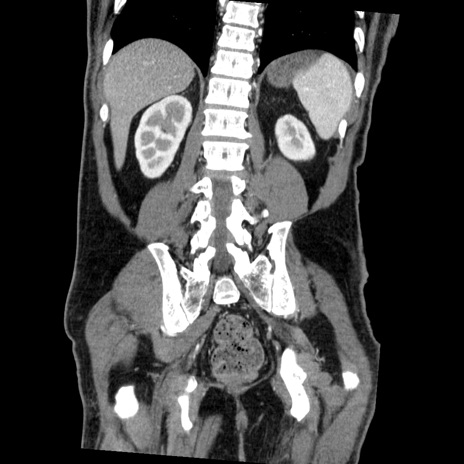

症例22(冠状断像)

【症例】50歳代男性

【主訴】腹痛

【現病歴】AVMからの被殻出血のため回復期リハ病棟入院中。 本日午後3時頃急に下腹部痛が出現した。

【既往歴】AVM、被殻出血、虫垂炎、高血圧

【身体所見】意識晴明、左半身不全麻痺、会話の理解は良好、36.5°C、腹部:膨隆、全体に板状硬、下腹部正中に圧痛点あり、反跳痛-、筋性防御不明、右下腹部にope scar

【データ】WBC 9400、CRP 0.06